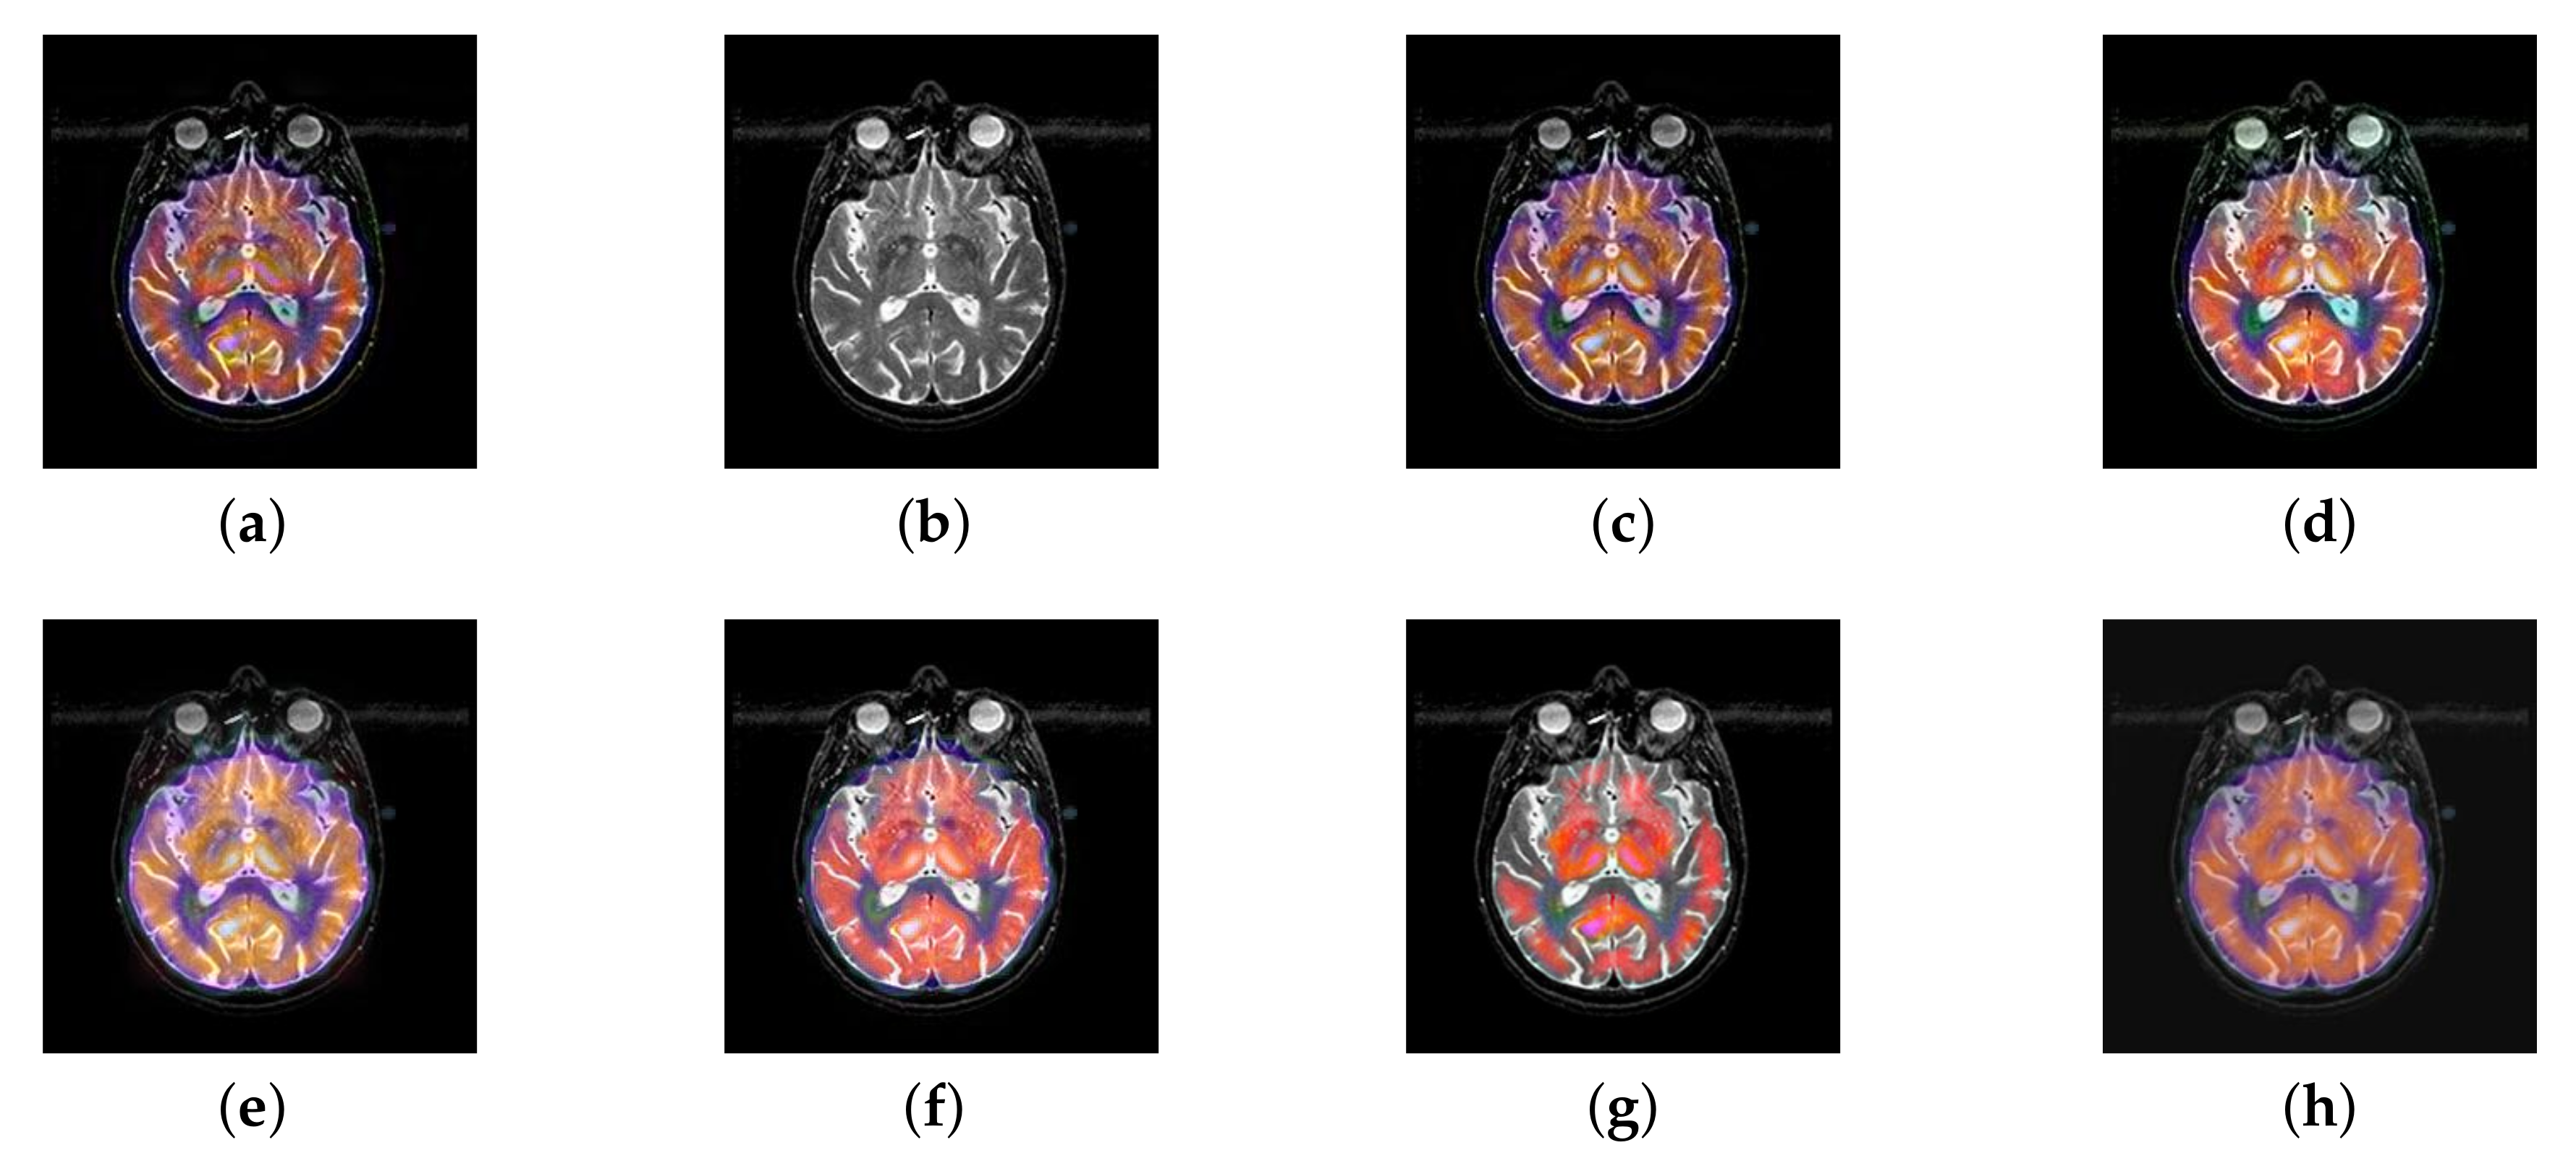

In this section, there are four multi-modal image sets and each set is consist of MRI image and SPECT image that are corresponding to the sanme location slice of the brain as shown in Figure 7. Among them, Figure 7e,f are captured from patients who have suffered a subacute stroke. Figure 7a–d,g,h are captured from patients who have brain tumor. The fused images with different fusion methods based on DTCWT, NSCT, GFF, LPSR, IGM, DDcGAN, FusionCNN, and the proposed methods are shown in Figure 8, Figure 9, Figure 10 and Figure 11. It can be seen that the fused images obtained by LPSR and FusionCNN algorithm have serious color distortion. Based on DTCWT and NSCT algorithm, the fusion image structure information is not obvious. The fused images obtained by GFF and IGM algorithm contain almost no color information, which is not conducive for doctors to make correct diagnosis. The image obtained by the DDcGAN algorithm saves the color information in the SPECT to a great extent; however, the brightness of the fused image is too large, which causes the image to have no sense of hierarchy and the contrast to decrease. By comparing with other algorithms, we find that our algorithm has good color retention effect, clear structure information, moderate brightness, and no artifacts.

Figure 8.

Fused medical images obtained by different algorithms (Figure 7a,b): (a) dual tree complex wavelet transform (DTCWT), (b) guided filtering fusion (GFF), (c) non-subsampled contourlet transform (NSCT), (d) Laplacian pyramid sparse representation (LPSR), (e) internal generative mechanism (IGM), (f) Fusion convolutional neural network based (FusionCNN), (g) dual-discriminator conditional generative adversarial network based (DDcGAN), and (h) FusionNet.

Figure 9.

Fused medical images obtained by different algorithms (Figure 7c,d): (a) DTCWT, (b) GFF, (c) NSCT, (d) LPSR, (e) IGM, (f) FusionCNN, (g) DDcGAN, and (h) FusionNet.

Figure 10.

Fused medical images obtained by different algorithms (Figure 7e,f): (a) DTCWT, (b) GFF, (c) NSCT, (d) LPSR, (e) IGM, (f) FusionCNN, (g) DDcGAN, and (h) FusionNet.

Figure 11.

Fused medical images obtained by different algorithms (Figure 7g,h): (a) DTCWT, (b) GFF, (c) NSCT, (d) LPSR, (e) IGM, (f) FusionCNN, (g) DDcGAN, and (h) FusionNet.